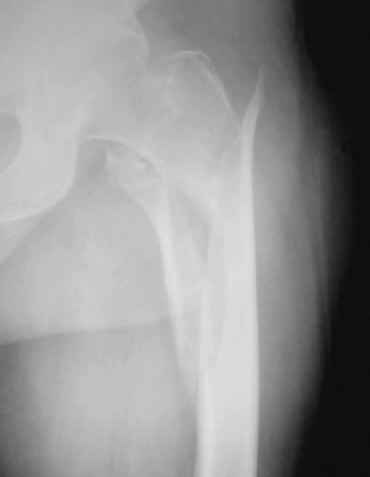

склоняемся к длинной версии вертельного гвоздя chm mm так 300.проблема в том что такой практики не было,может есть какие нибудь руководства по имплантации такого гвоздя?какие могут возникнуть поблемы и технические трудности.буду признателен за любую информацию.спасибо.очень хотелось бы узнать мнение А.Н Челнокова!

коллеги в наличии есть только проксималный гвоздь chm длинна 260мм.отправить мы ее тоже никуда не можем т.к в облати внедряется тока у нас

Короткая версия 240 мм. Длинные начинаются с 260 мм? Попробуйте имеющуюся железку приложить к рентгенограмме - скорее всего, 260 мм будет маловато. Должна быть возможность связаться с поставщиком и поменять имеющийся гвоздь на аналогичный нужного размера.

Мда...не самый удачный случай для начинаний... Думаю, 260 мм здесь явно не подойдет(коротковат), перед разрезом добивайтесь максимально возможной репозиции на столе, определитесь с точкой введения штифта(это принципиальный момент), если физически этой точки не существует, то все равно вводите штифт через то место, где она должна была бы быть, постарайтесь вводить штифт ориентируясь по наружному кортикалу и ни в коем случае не идите диагонально. Сам клинок вводите под контролем в аксиальной проекции (естессно, сначала смотрим спицу в прямой). Удачи!)))

День добрый! 240 мм однозначно короток, нужен миниум 300 мм, а то благие начинания заведут вас в ад осложнений. С диабетом на операции открывть ничего не нужно, только закрытая репозиция на ортопедическом столе под контролем ЭОПа. Без 100% анатомичной репозиции. Восстановить ось и ШДУ.